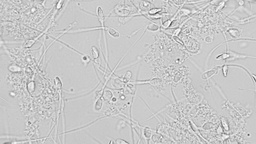

Espermatobioscopía (Seminograma)

760.00

Precio Tienda Virtual

734.00

Precio promocion

708.00

Precio LapiFan

734.0 MXN